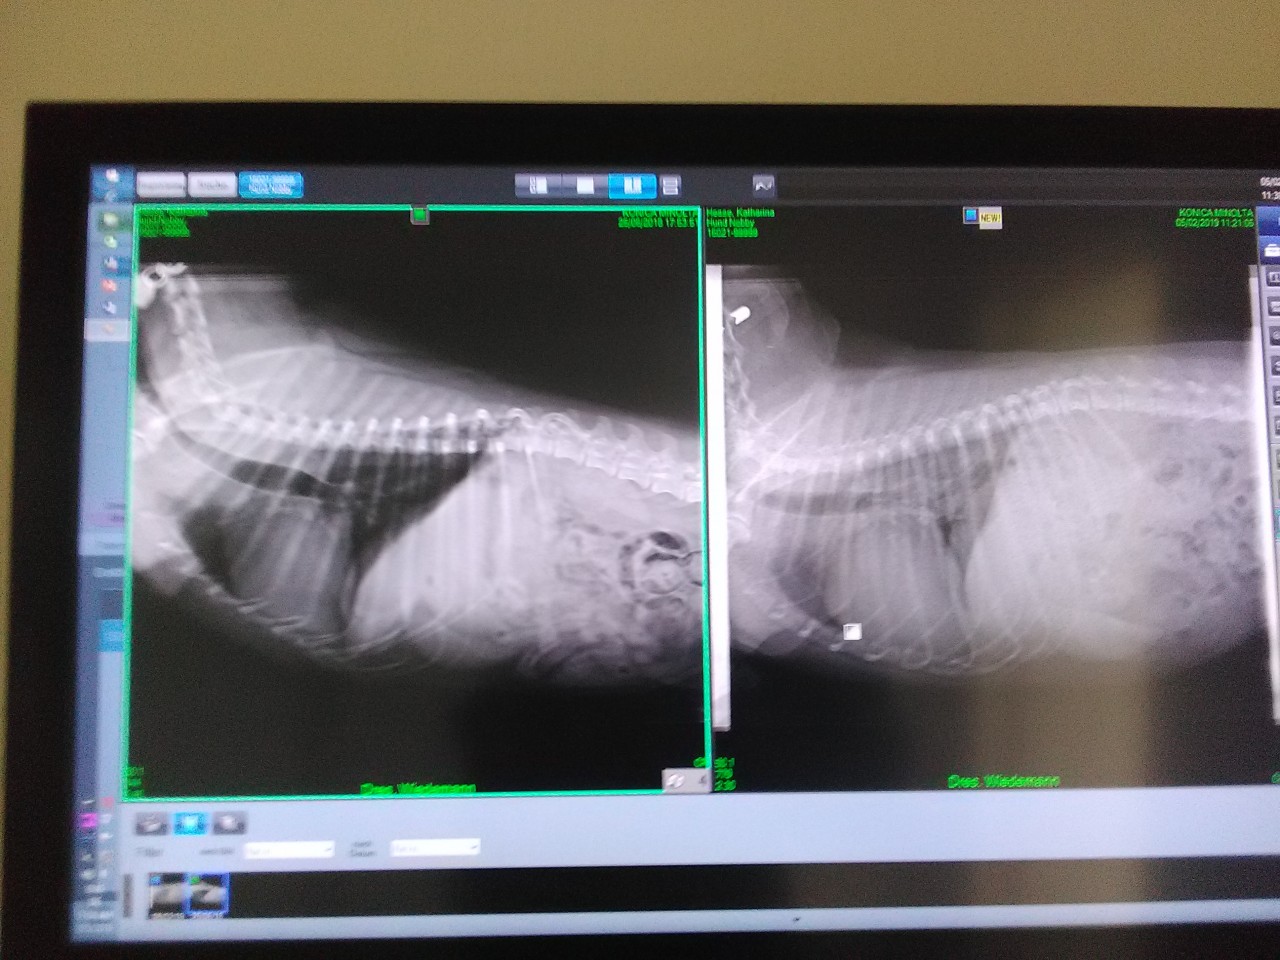

War dann gestern beim Arzt, haben dann gleich geröntgt...Naja also wir hatten einen guten Vergleich, weil wir vor nem 3/4 Jahr schonmal geröntgt haben...

War kaum noch schwarz zu sehen... also das rechte Bild ist das neue...hänge das Bild Mal mit Ran...